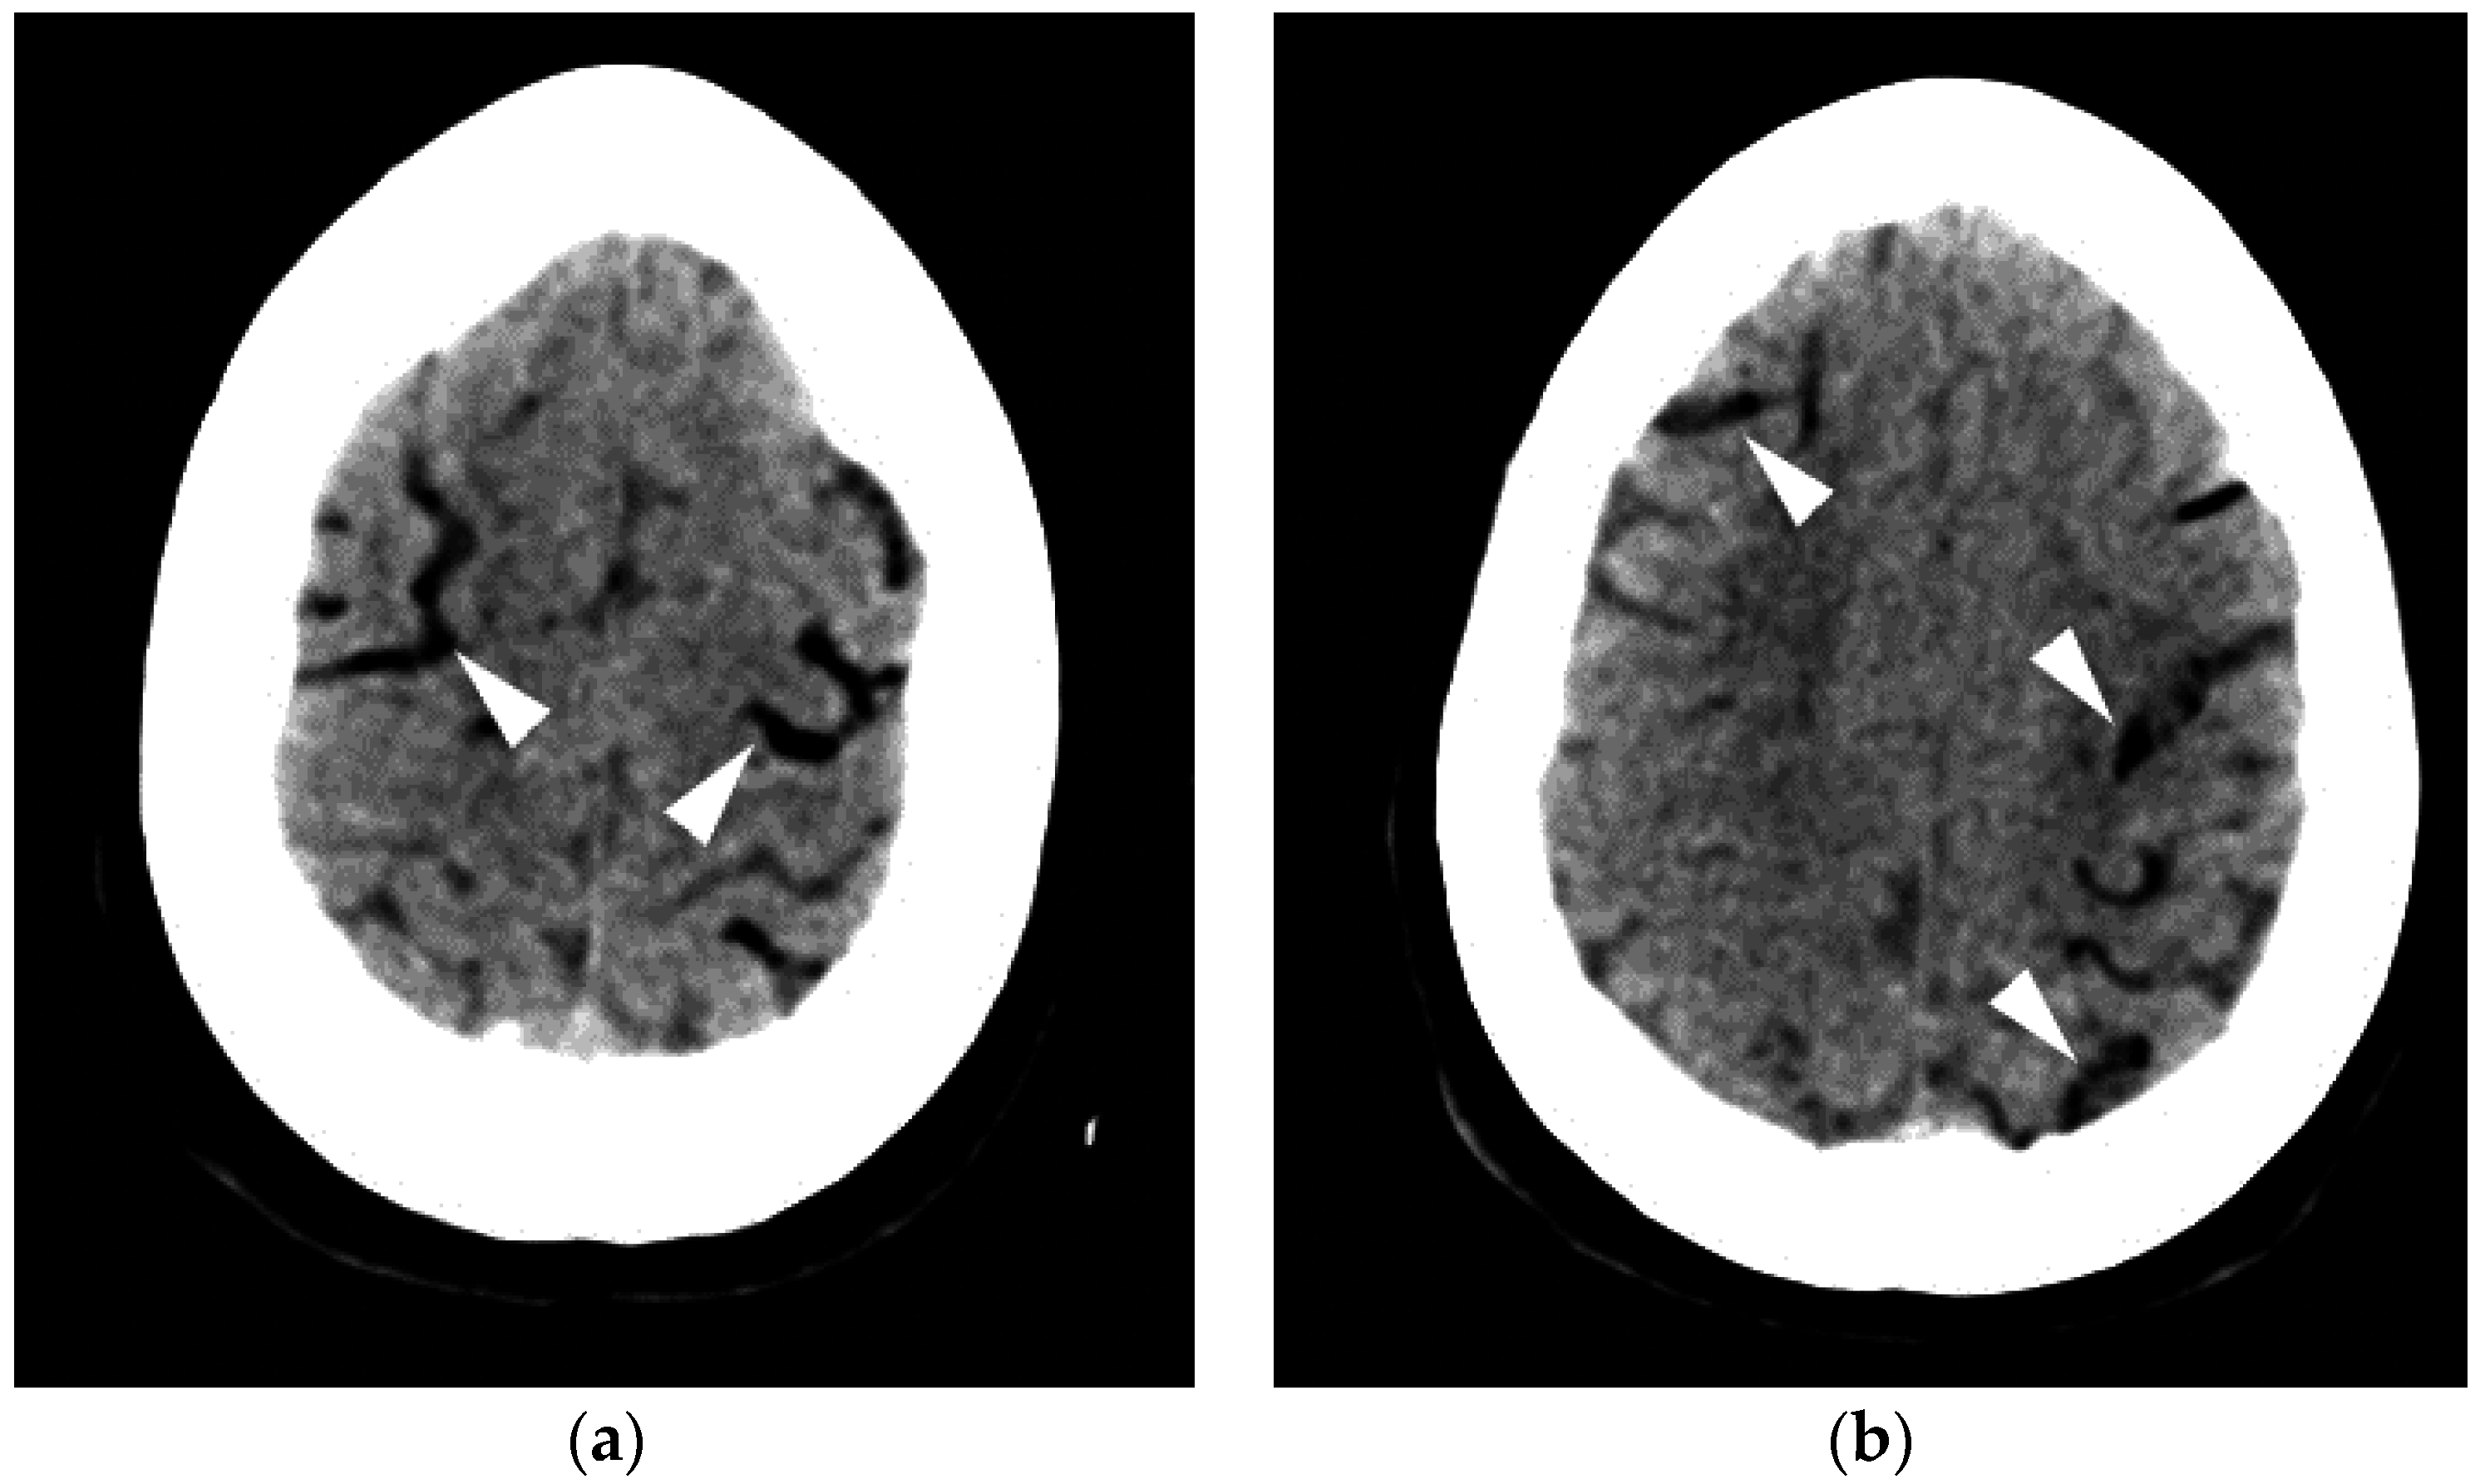

Figure 1.

A 35-year-old man was transferred from an outside hospital with altered mental status following the placement of a peripheral intravenous line. A CT of the brain was performed in the emergency room. Axial (a) and coronal (b) CT revealed a moderate amount of air in the cavernous sinuses bilaterally (arrows) as well as multiple small foci of air in the region of the pterygoid venous plexuses (c), scattered in the soft tissues and in the extradural space at the level of the upper cervical spine (arrowheads). A follow-up CT (d) was performed the next day, which revealed resolution of the previously seen air. In this case, the patient made a full recovery.